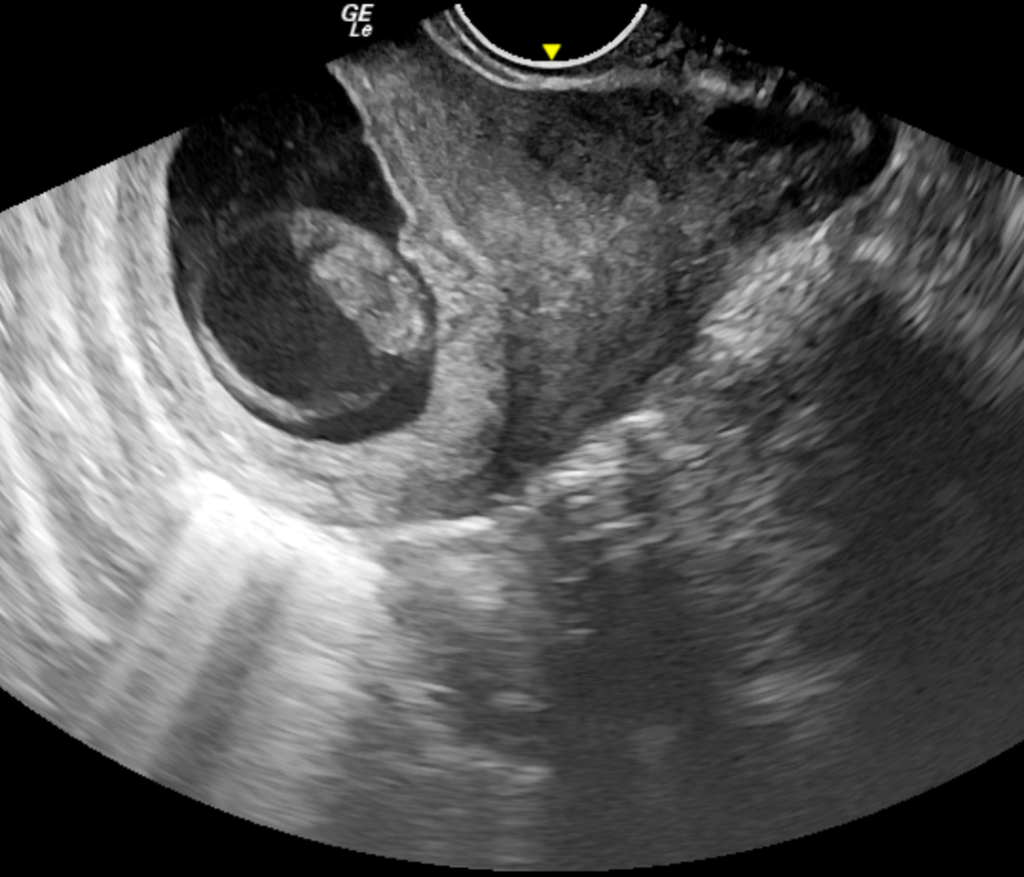

We report a case of a 24-year-old lady who was unable to conceive for a period of 8 years. Infertility workup was negative. In 2018, she conceived, however cardiac activity was not demonstrated in the fetus and eventually medical abortion was performed. Transvaginal sonography was performed for the same at a private center which did not pick up any uterine structural abnormality. In 2021, the patient presented to our emergency department with a 14-week gestation pregnancy with complaints of bleeding per vaginum for 2 days. Antenatal transvaginal ultrasound was performed for confirmation and viability of an intrauterine pregnancy. An intrauterine gestational sac with crown rump length corresponding to 8 weeks 5 days and absent cardiac activity was seen suggesting the diagnosis of missed abortion (Figure 1). Surrounding the gestational sac was fluid with internal echoes suggesting failure of implantation (Figure 2). A well-defined uniformly echogenic pedunculated lesion was seen in the endometrial cavity (Figure 3). As it was traced towards the point of its origin, a focally hypoechoic region was demonstrated interrupting the hyperechoic endometrial lining (Figure 4), classically described as the ‘interrupted mucosa sign’ [2]. On colour doppler image, a single vascular pedicle was demonstrated (Figure 5), known as the ‘pedicle artery sign’ [3]. Based on these classical features the diagnosis of an endometrial polyp was made. It was seen to abut the gestational sac suggesting mechanical hindrance to growth of the embryo (Figure 6). On real time imaging, the endometrial polyp was seen prolapsing from towards the uterine fundus to the lower uterine segment (Figure 7). For better characterization of the endometrial polyp, it has been recommended to distend the uterine cavity with saline (also known as saline infusion sonohysterography) [4,5], however in our case it was unwarranted because the gestational sac and fluid naturally distended the uterine cavity and helped in optimum visualization (Figure 4,6). Figure 8 depicts another case of an endometrial polyp showing a non-gravid uterus with an echogenic lesion in the endometrial cavity showing the classical interrupted mucosa sign (Figure 8A) and the feeding artery sign (Figure 8B).

Figure 3: Transvaginal sonography A) Sagittal section B) Axial section show a well defined, well contoured, homogenously hyperechoic lesion in the endometrial cavity with a stalk suggestive of endometrial polyp.

Figure 6: Axial section of transvaginal sonography depicting the mechanical hindrance to implantation and growth of fetus by the well defined polypoidal lesion. Also note the natural distension of endometrial cavity by fluid in gestational sac and endometrial cavity beautifully delineating the polyp margins thus obviating the need for saline infusion in this case.